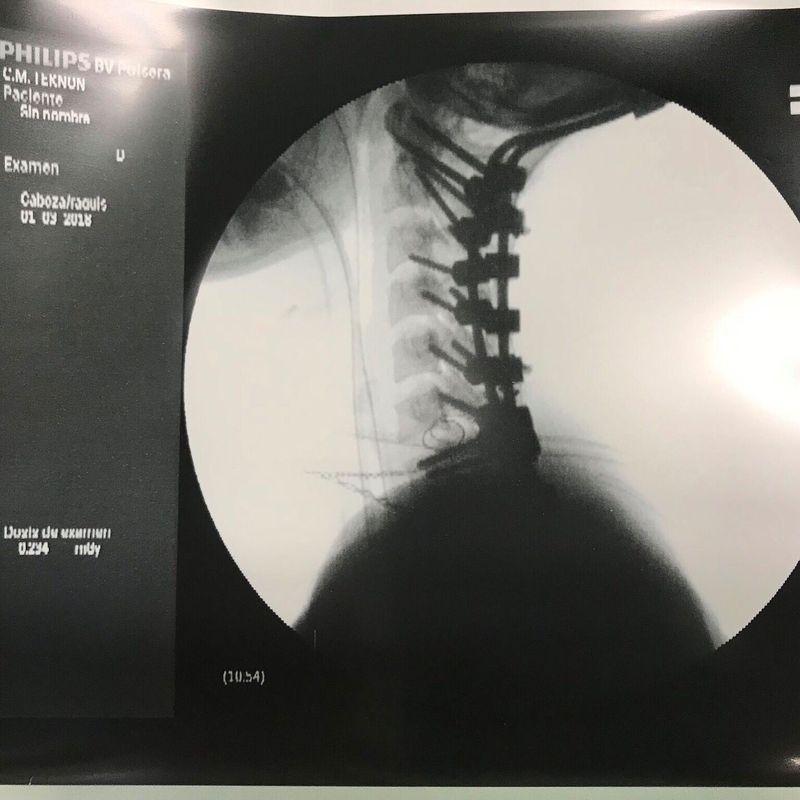

What surgeries could this patient have had and what conditions warrant them?

Spinal fusion. Also the skull is connected. Those kind of surgeries are made to prevent dislocation of vertebrae or skull on Atlas (it could happen when patient have rheumatoid arthritis).

Could this also be a treatment for someone with severe internal decapitation?